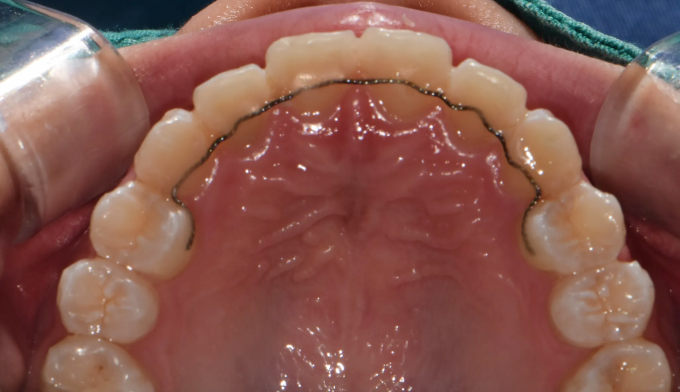

초등학생때 1차교정을 통해 앞니만 배열하였다고 했습니다.

진단해보니 송곳니가 나올 공간이 부족하여 2차교정을 진행하였습니다.

그래도 1차교정을 통해 공간을 어느정도 확보해 놓은것이 2차교정을 더 수월하게 해줍니다.

남아있는 공간을 최대한 활용하여 발치없이 치아를 배열해줍니다.

교정기간은 14개월 소요되었습니다.